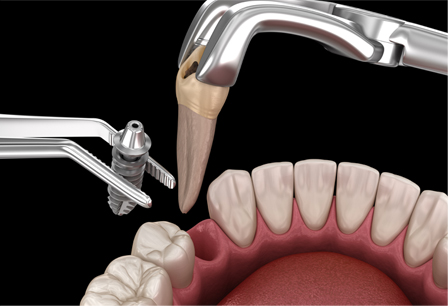

발치즉시 임플란트

발치 즉시 임플란트는 방문 당일 발치 후 식립까지 도와드리는 신속한 임플란트입니다. 기존 임플란트 시술과는 달리 치아를 발치한 후 시간 경과 없이 바로 식립하여 치료 기간을 단축하고 뼈손실을 줄일 수 있습니다.

발치 즉시 임플란트의 특별함

뼈 재생에 유리한 조건 완성

총 2회에 걸쳐 진행하는 수술을 단, 1회만에 진행하여 뼈가 재생하는데 훨씬 유리한 조건으로 바꿔드립니다.

현대인에 적합한 치료시간

치료시간을 절반 이상 단축하여 바쁜 현대인도 빠르고 편안하게 식립할 수 있습니다.

정교한 식립 노하우

발치 즉시 임플란트는 고난도 실력이 필요합니다. 오스카55플란트치과는 정교한 발치와 식립 노하우로 식립해드립니다.